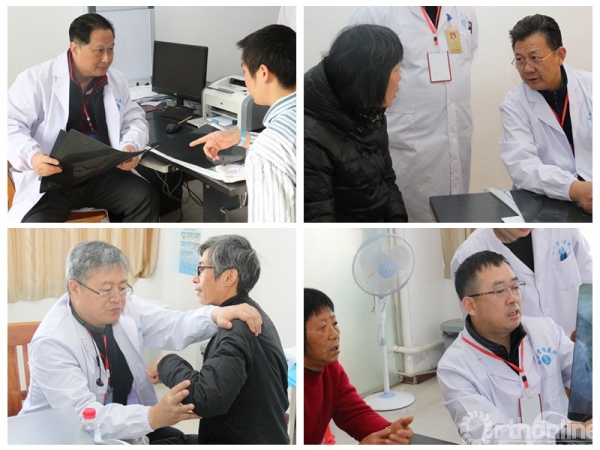

医者仁心——义诊活动

9日上午,专家们为慕名前来的当地及周边地区患者,进行了义诊活动,来自全国各地的运医大家,纷纷严肃认真的的诊病,温暖和煦的询问,为当地民众切实解决所存在的疾患。专家与当地的医生及病患积极互动,从问诊、诊断、阅片等方方面面仔细认真对待,处处彰显大家风范。

△义诊现场

△义诊现场

一上午时间,专家们针对80余位病人的情况分别提出了自己的治疗建议。各位专家针对不同的病人情况,给出了不同的治疗建议,有些建议保守治疗,有些建议进一步检查治疗。对有些多年活动受限的患者,专家当即给出适当的治疗方法,帮助病人活动,在短短几分钟的时间里,患者的功能活动度就有很大的提高。